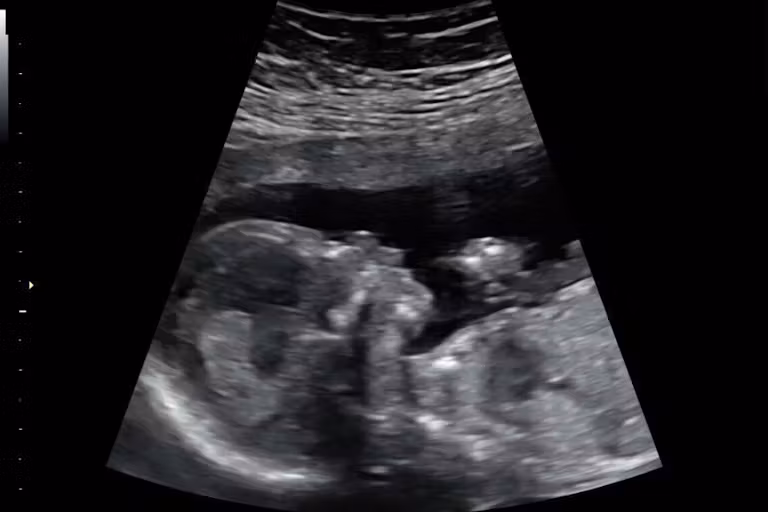

In a circulating social media video, a Texas woman named Ruby claims she went into cardiac arrest during a miscarriage (confirmed days earlier by an ultrasound which revealed her child had died in utero) before doctors finally decided to perform a D&C. She blamed the state's pro-life law, despite the fact that the law does not prohibit D&C procedures for miscarriages.

1757975632-baby-evans-1-ultrasound